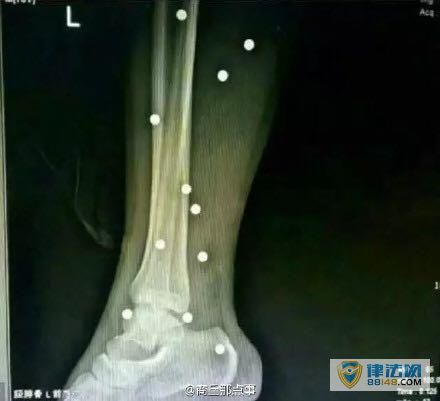

网传伤者腿内的钢珠。

“三人轻伤,两位重伤者当晚在神火医院拍了片子立即转徐州二院。一位重伤者体内有47颗钢珠其中还有铁丝,腿部直接被震骨折,颈部大动脉处及脚踝动脉处钢珠未取,现只取出29颗。另一位伤者体内有21颗钢珠现腹腔内仍有钢珠未取,手术持续八个小时,两位伤者才被送出手术室,直接送入重症监护室。”当地资讯博主@商丘那些事 描述道。